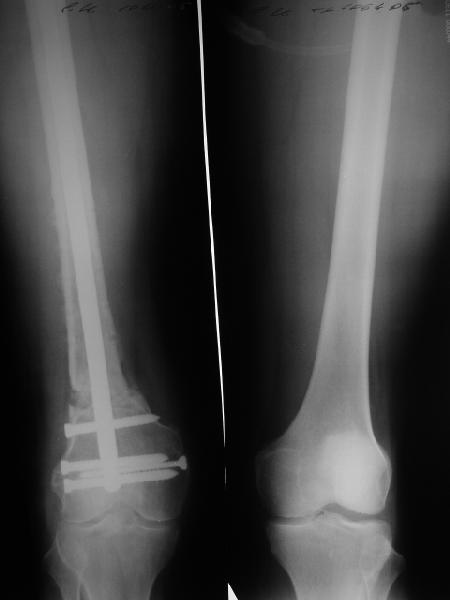

В приложении как раз видна эволюция использововшихся у нас большеберцовых гвоздей. Первый - дизайн как у UTN, второй - разнесены 45 градусные отверстия (зачем их вообще изначально так нелепо на одном уровне сделалм???), третий - убрано сиавшее лишним статическое отверстие, Herzog's bend перемещен более проксимально.